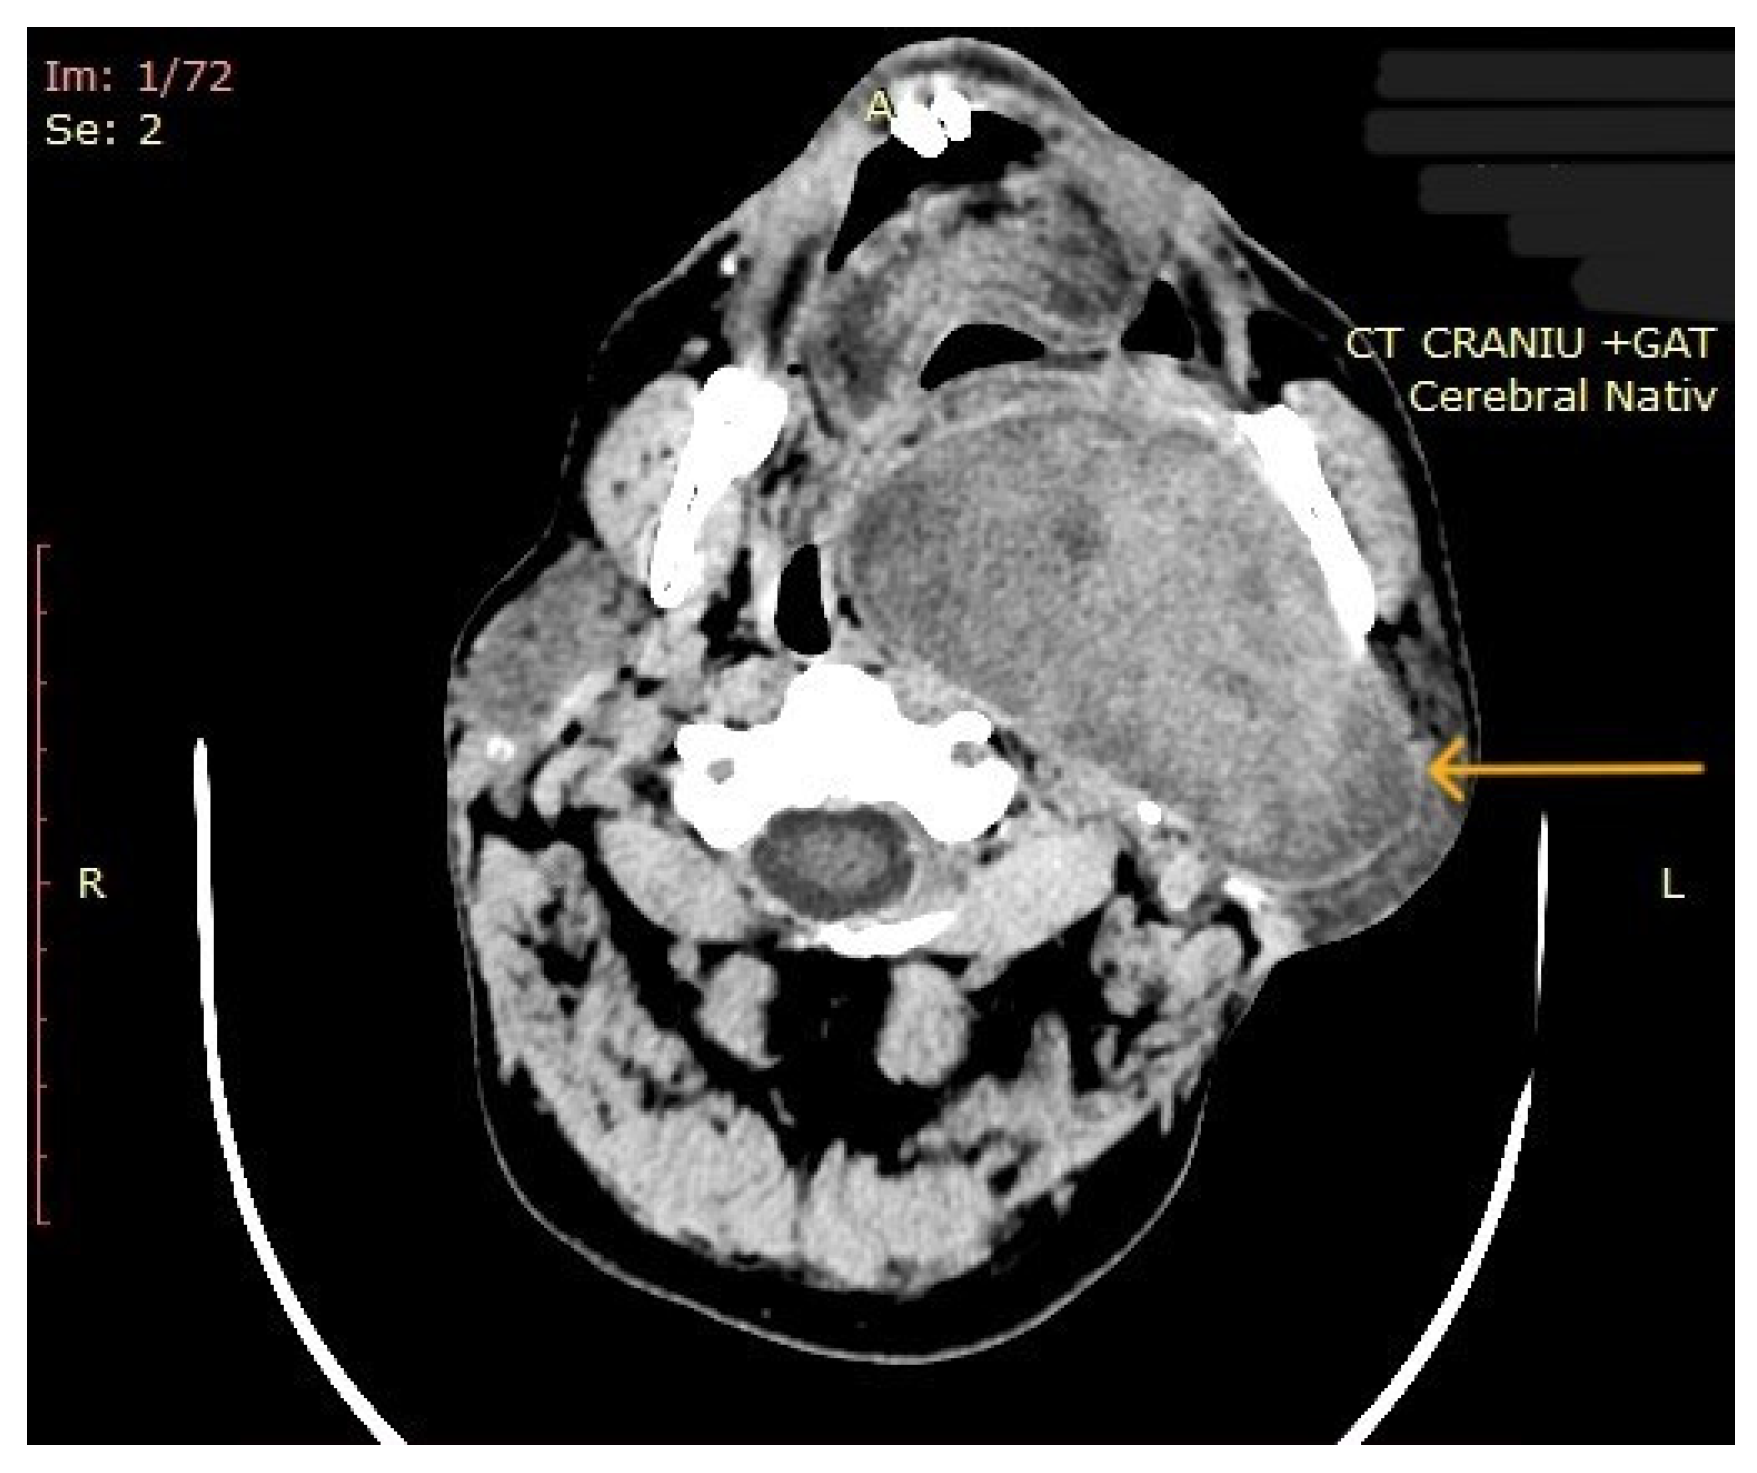

| 10 | Left parapharyngeal region with maxillary and intracranial extension | Discomfort in breathing, chewing, swallowing, phonation, sleeping, regional pain, fatigue | 5 years | 10 cm | Benign tumor of soft tissue |